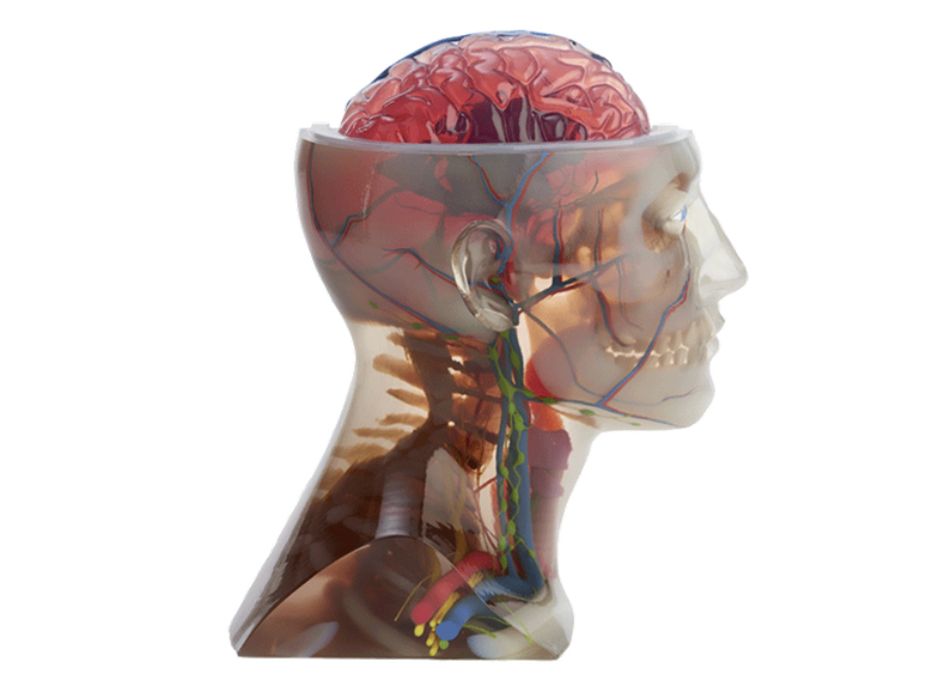

Researchers Demonstrate Volumetric Color 3D Printing With Translucent Fidelity

Researchers have developed a way to 3D print true volumetric color objects.

Examining Mixed Dimension’s Anatomical 3D Prints

I got my hands on a fantastic full color, transparent 3D print from Mixed Dimensions and it’s worth discussing.